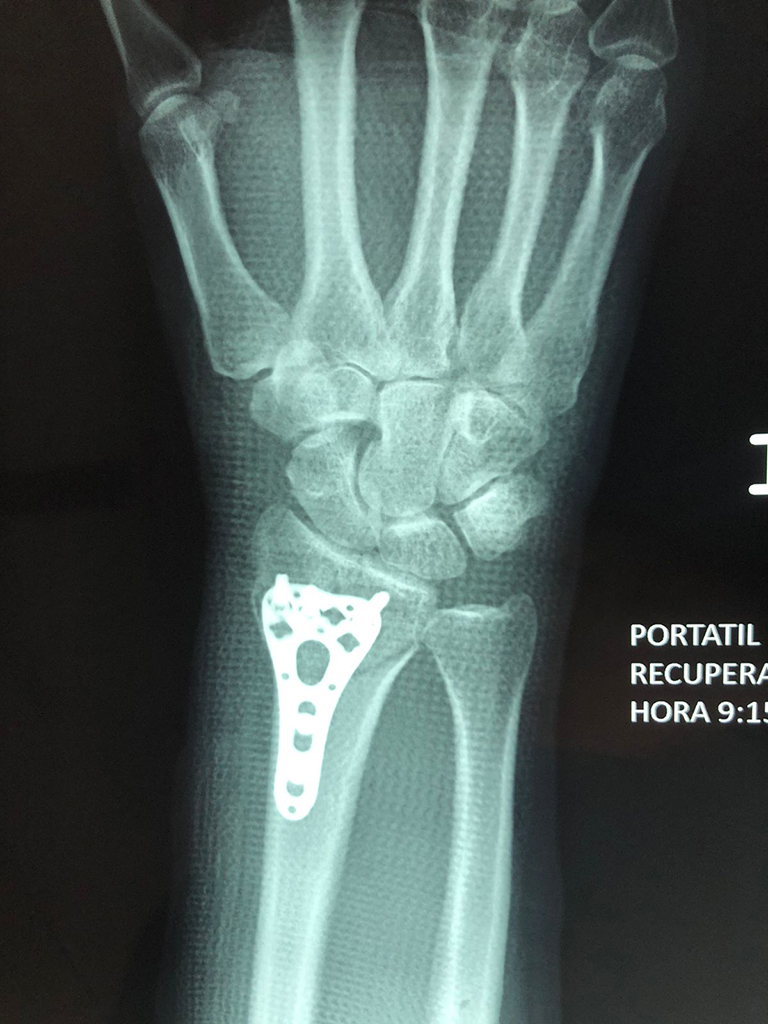

Cirugía de Muñeca y Mano

Los procedimientos más comunes en cirugía de la mano son aquellos destinados a reparar traumatismos, incluyendo lesiones de tendones, nervios, vasos sanguíneos, y articulaciones; huesos fracturados; y quemaduras, cortes, y otros daños de la piel.